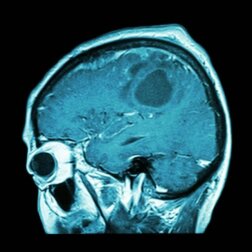

Sarà possibile, un giorno, disporre di un vaccino per il tumore al cervello? I vaccini rappresentano un ottimo sistema di prevenzione e consentono anche di curare alcune malattie. Non è dunque assurdo che i ricercatori analizzino diverse possibilità per debellare neoplasie aggressive come il tumore al cervello. E se ci fosse già un vaccino?

Forse, però, non abbiamo più motivo di preoccuparci per eventualità come questa. Sono molte le fonti che ci informano dell’esistenza di un vaccino che potrebbe costituire la soluzione definitiva contro il tumore al cervello. Vediamo quali sono le aspettative disponibili e in che modo questo vaccino agisce nella distruzione della massa tumorale.

Nel giugno del 2018, il quotidiano Il Fatto Quotidiano pubblicava una notizia che parlava di vaccini personalizzati per pazienti affetti da tumore al cervello. La sperimentazione è stata condotta attraverso uno studio che ha coinvolto un numero limitato di persone e che ha dato risultati piuttosto incoraggianti.

Tuttavia, proprio a causa del ridotto numero dei soggetti che hanno partecipato alla sperimentazione, i ricercatori non possono affermare con decisione di essere riusciti a scoprire la cura per questo cancro. Per confermarne l’efficacia, bisogna eseguire ulteriori ricerche.

I ricercatori, però, hanno scoperto che i tumori non sono tutti esattamente uguali e non tutti rispondono bene al trattamento mediante immunoterapia. Per questo motivo, gli sforzi sono stati orientati verso una “immunoterapia di precisione” per trattare pazienti che soffrono di glioblastoma.